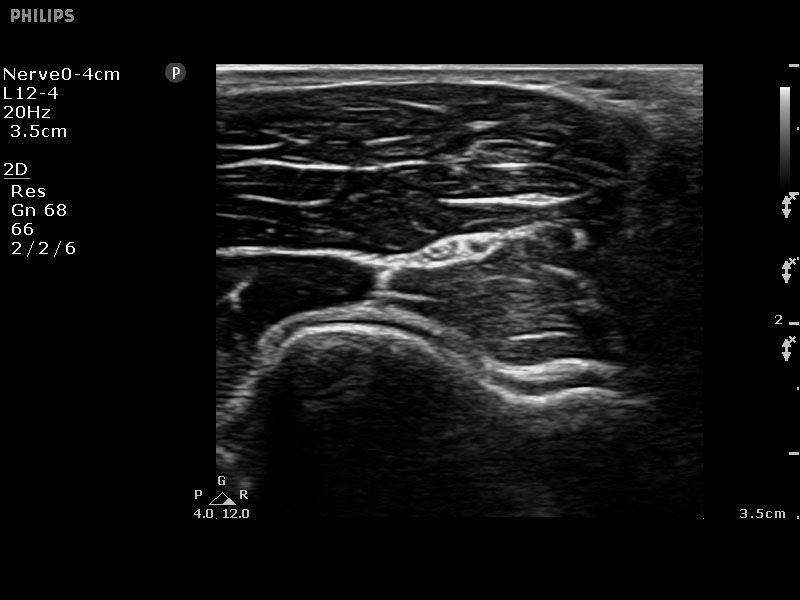

Die Nadelvisualisierung verbessert die Darstellung der Nadel ohne Verschlechterung der Bildqualität und erleichtert somit eine rasche und exakte Nadelführung zur anatomischen Zielregion. Um bei einer Punktion den Abstand zum Ziel besser einschätzen zu können, verfügt das System über eine Gitternetzanzeige.

Sparq bietet eine breite Palette klinischer Anwendungen speziell für die Innere Medizin, Notfallmedizin, Intensivversorgung, ultraschallgeführte Regionalanästhesie und Schmerzmedizin, einschließlich Interventionen an Nerven, Wirbelsäule, Muskel-Skelett-System, Gefäßen, Herz und Lunge sowie mittels TEE.